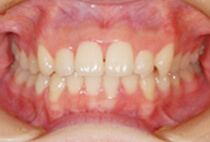

前歯のガタガタを気にして来院されました。なるべく抜かずに、短い治療期間で矯正治療を終わらせる治療をご希望されました。スピード矯正治療で、なるべく早期に前歯の審美性を改善することにしました。

上顎のみの舌側矯正治療ですが、下の歯には治療後半の噛み合わせを調節する段階で装置をセットしました。コルチコトミーを行ったことで、1ヶ月後には前歯のガタガタが大幅に改善できました。また、治療期間の短縮でけでなく、非抜歯できれいな歯並びに治療できました。

20代 女性

1年2ヶ月

18回

1,379,400円(+コルチコトミー121,00円)+毎月調整代7,260円